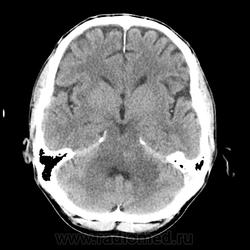

КТ ГМ+C Субтенториальное объемное образование в стволе головного мозга (мост)

Мужчина 46 лет. Поступил с подозрением на ОНМК. Жалобы на шаткую походку, снижение зрения. Мост содержит ядра ЧМН (V, VI, VII, VIII). Для невриномы и менингиомы не  характерна локализация. Узловое, экспансивно растущее образование, интенсивно накапливает КВ. DDs: Кавернозная ангиома, mts.

Кажется кавернома. Для такого мтс хотелось хоть минимальеого отека. Но кто знает. На мрт.

Ну да, перифокального отека нет, лишь IV желудочек компремирован. МРТ точно рассудит.

Кавернома контраст накапливает?

А отёка точно нет?

Да, а контраст то не должна копить, а в случае хронической гематомы только по перифирии.

Да как то не выражен, может незначительный, IV желудочек не резко  деформирован и сужен.

По-моему отека предостаточно.

мост и левая средняя мозжечковая ножка гипо-, цистерн ЗЧЯ вообще не видно...

Отека то может  и не быть, а вот границы у этой опухоли довольно таки четкие для mts, хотя... будем искать или исключать основную опухоль.

У Трофимовой " Можно наблюдать КУ" очень размыто написано,  непонятно какое КУ слабо выраженное или интенсивное, гомогеное или гетерогенное? Больше Пронину и Корниенко доверяю, а они утверждают, что либо КУ не определяется, либо слабо выраженный характер, даже точечный.  А в данном случае я не могу сказать, что контраст копит слабо...хорошо так копит, потому и подумал больше в сторону mts. В любом случае  МРТ я порекомендовал.